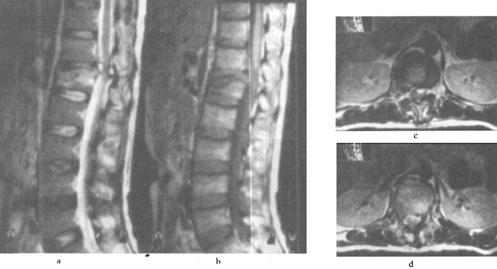

(2)出血:包括脊髓内出血和硬膜外血肿(图7-14至图7-16)、硬膜下出血和蛛网膜下腔出血等。脊髓内出血是不可逆损伤,其信号改变随时间变化较大。急性期(24h内)髓内出血灶在T1WI呈中等信号或不均匀信号,在T2WI呈中央低信号出血灶,外围水肿为高信号。亚急性期(3~5d)血肿在T1WI信号逐渐升高,在T2WI信号仍较低,慢性期血肿在T1WI和T2WI均为高信号。脊髓硬膜外血肿、硬膜下出血和蛛网膜下腔出血,在MRI上表现为椎管内脊髓外的软组织增厚影,在T1WI呈不均匀低信号,在T2WI为高信号。硬膜外出血脊髓受压移位明显。

图7-14 腰椎后柱骨折伴硬膜外出血,马尾受压。T1W(a)和T2W(b)矢状成像,椎管后方硬膜外可见T1W和T2W均为高信号的血肿

图7-15 颈髓挫裂伤:T1W(a)T2W(b)矢状面,脊髓增粒为髓水肿所致,T1W和T2W信号增高。横断面(c)脊髓内可见斑片状出血灶,硬膜外血肿T2W亦呈高信号,脊髓压迫向右后移位。颈后方软组织出血水肿,在T2W亦为高信号

图7-16 L1压缩骨折,脊髓挫裂伤:T1W(a)和T2W(b)矢状面,L1椎体呈楔状变形,椎体骨折,但无移位。后方硬膜外及脊髓内可见高信号血肿,在横断位T1W(c)、T2W(d)成像,如箭头所示脊髓圆锥内椭圆型高信号影,为出血所致。椎体骨髓水肿及出血。